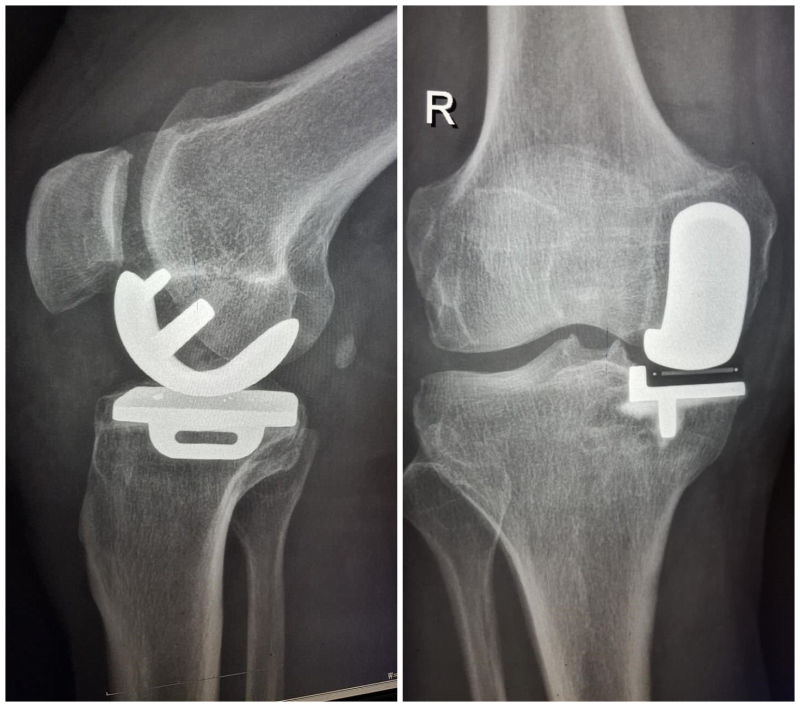

9月4日,我院骨外一科成功完成首例膝关节单髁置换术。患者术后疼痛及膝关节功能明显好转,效果显著。该手术的成功,不仅填补了我县骨科领域的技术空白,同时标志着我院在人工关节置换技术方面又上了一个新台阶。

患者,杨先生,63岁,系本县一名退休职工,因右膝关节疼痛半年余收住入院。半年前,杨先生右膝关节前内侧出现隐痛不适,劳累后疼痛加重,休息后症状可缓解,近来杨先生自觉疼痛逐渐加重,慢慢竟发展至不敢下床活动,曾前往济南某医院就诊,诊断为“骨性关节炎”,建议其行膝关节单髁置换术。于是,杨先生于9月2日来到我院就诊,门诊拍片后以“右膝关节骨性关节炎”收住入骨外一科住院治疗。入院检查发现患者右膝关节轻度内翻畸形,不能完全伸直及屈曲,膝关节前内侧间隙压痛明显。磁共振检查显示:右膝关节退变,内侧半月板损伤。骨外一科主任、副主任医师刘波随即召集科室技术骨干进行术前讨论并制定手术方案,于9月4日成功为患者实施手术。术后第一天患者已能下床活动,目前,患者膝关节功能恢复良好。

据悉,膝关节单髁置换术较全膝关节置换术更加微创,仅对胫股关节单侧病变间室进行表面置换,不干扰膝关节其他正常或近乎正常的部分,从而以最小的创伤获得最大的收益,解决困扰病人的主要问题。单髁关节置换术创伤小、术后恢复快、并发症少、术后功能好,还保留了膝关节前后交叉韧带及本体感觉,术后病人的感觉好,活动更自如。随着科学技术日新月异,关节手术微创化将成为发展趋势,越来越受到患者的青睐。